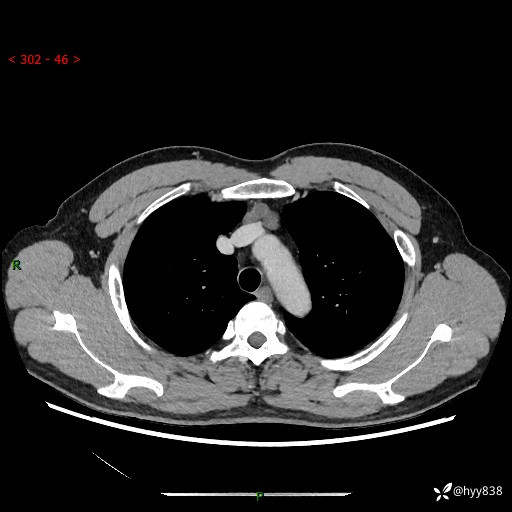

患者性别:女

患者年龄:49岁

简要病史:跟骨骨折,常规CT发现纵隔占位

胸部CT平扫

增强(动脉期+静脉期)